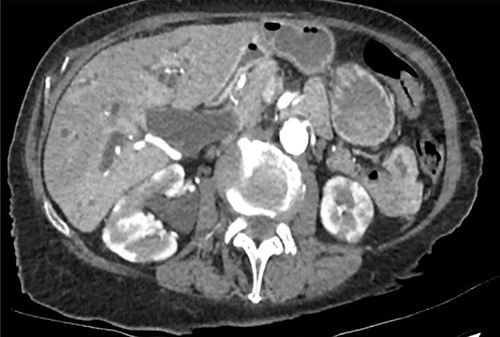

An 83-year-old woman was referred to our hospital for investigation of a 10-day history of obstructive jaundice, lethargy and weight loss. An abdominal computed tomography (CT) found a complete obstruction of the mid common bile duct (CBD) (Fig. 1), as well as multiple intrahepatic biliary strictures, an enlarged pancreas and multiple hypodense wedge-shaped lesions in both kidneys. IgG4-RD was suggested as a unifying diagnosis of these findings, but cholangiocarcinoma could not be ruled out.

CT abdomen—complete obstruction of mid-CBD, intra and extrahepatic biliary duct dilatation; no obstructing lesion identified; enlarged pancreas with abnormal enhancement and hypodense rind; diffuse hypodense wedge-shaped lesions in bilateral kidneys.